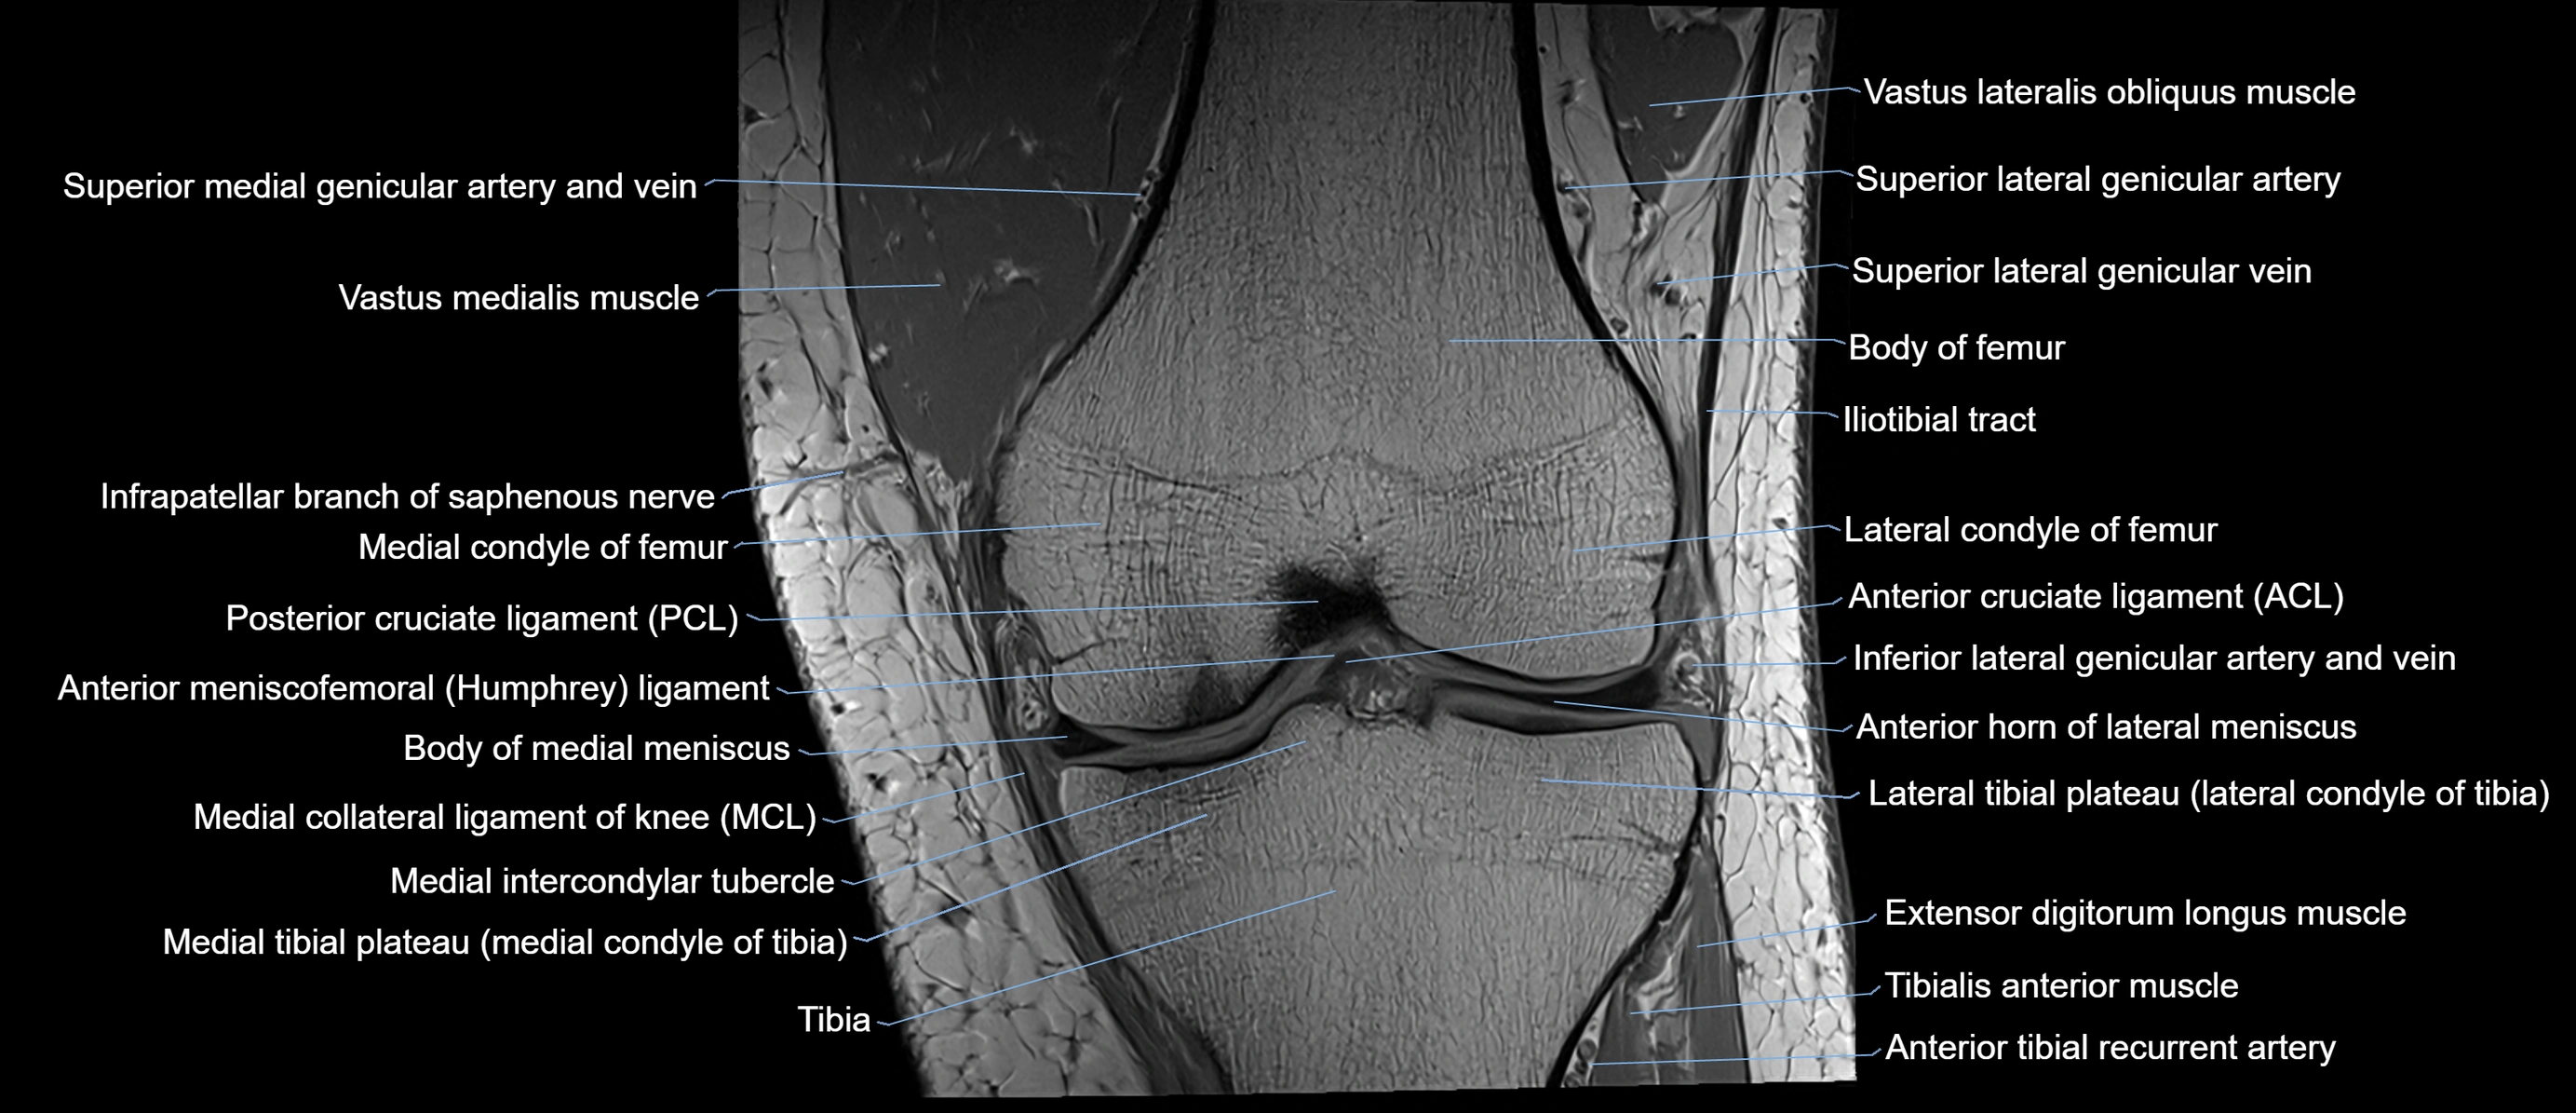

- Anterior cruciate ligament

- Anterior horn of lateral meniscus

- Anterior meniscofemoral ligament

- Body of medial meniscus

- Extensor digitorum longus muscle

- Infrapatellar branch of saphenous nerve

- Lateral condyle of femur

- Lateral condyle of tibia

- Lateral tibial plateau

- Medial collateral ligament

- Medial condyle of femur

- Medial condyle of tibia

- Medial intercondylar tubercle

- Medial tibial plateau

- Patellar tendon (patellar ligament)

- Posterior cruciate ligament

- Superior lateral genicular artery

- Superior lateral genicular vein

- Tibia

- Tibialis anterior muscle

- Tubercle of iliotibial tract

- Vastus Lateralis Obliquus Muscle

- Vastus medialis muscle